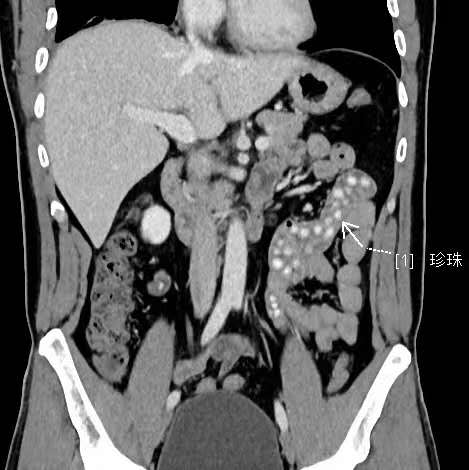

拍出來的片子讓醫(yī)生大吃一驚,小林的胃腸道里布滿了高密度陰影。仔細(xì)一看,醫(yī)生發(fā)現(xiàn)是一顆顆沒有消化的東西,像珍珠奶茶里面的“珍珠”。

“密密麻麻,粗略估計(jì)有幾十顆。”影像科副主任醫(yī)師薛貞龍告訴現(xiàn)代快報(bào)記者,奶茶里的珍珠很難消化,CT顯示腸腔內(nèi)圓形結(jié)節(jié)狀高度密影。他提醒,對(duì)于炎性腸病患者,尤其是伴有輕中度腸道狹窄的患者,最好別喝奶茶,很容易誘發(fā)腸梗阻。